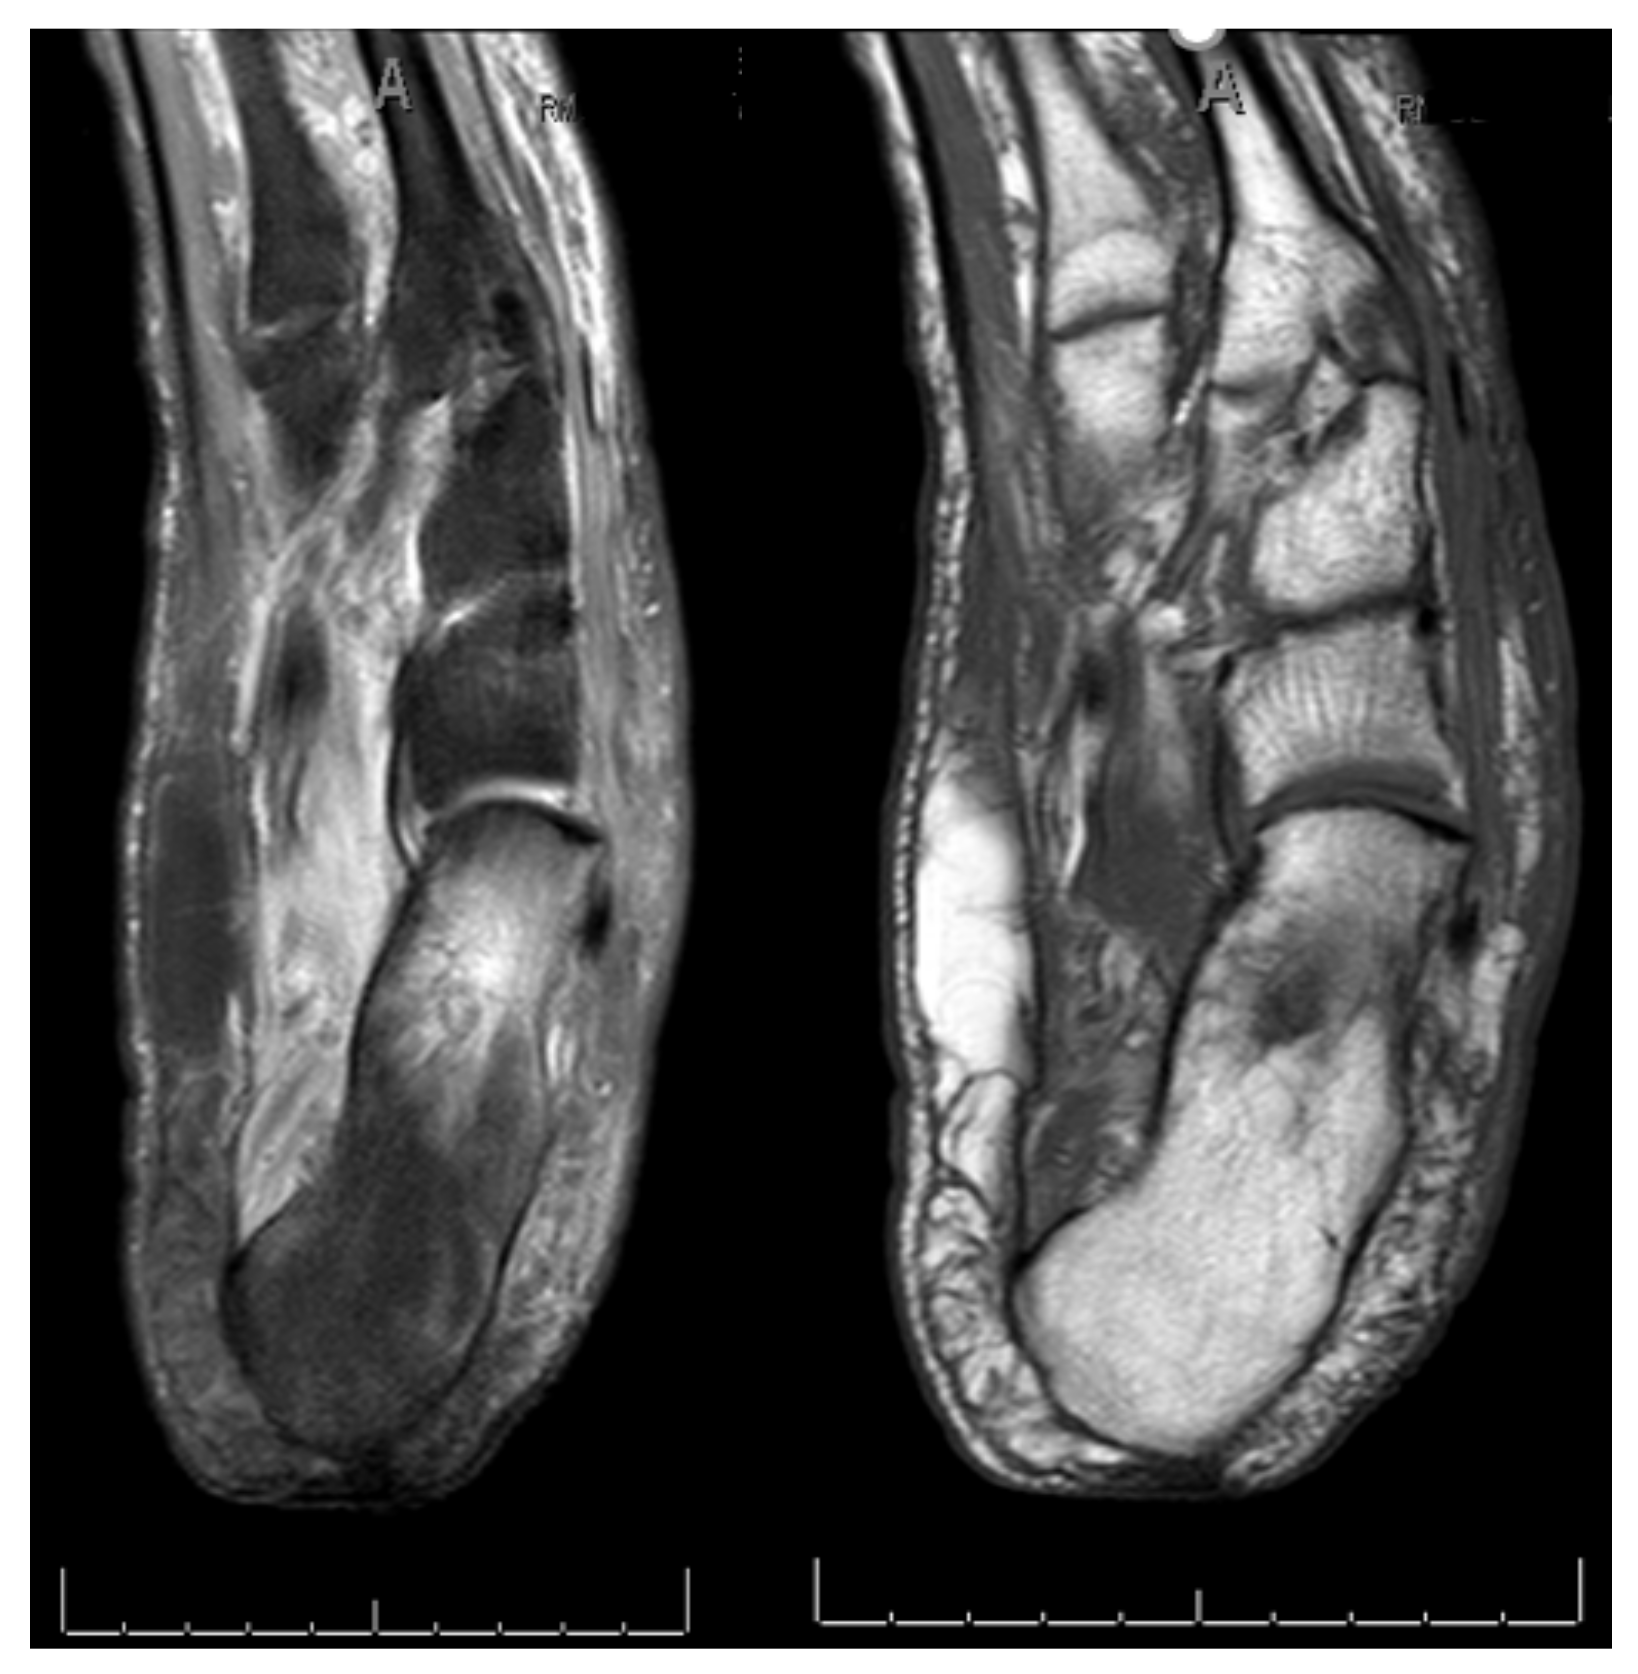

3.3. Lesions Involving Distal Tarsus & Talus